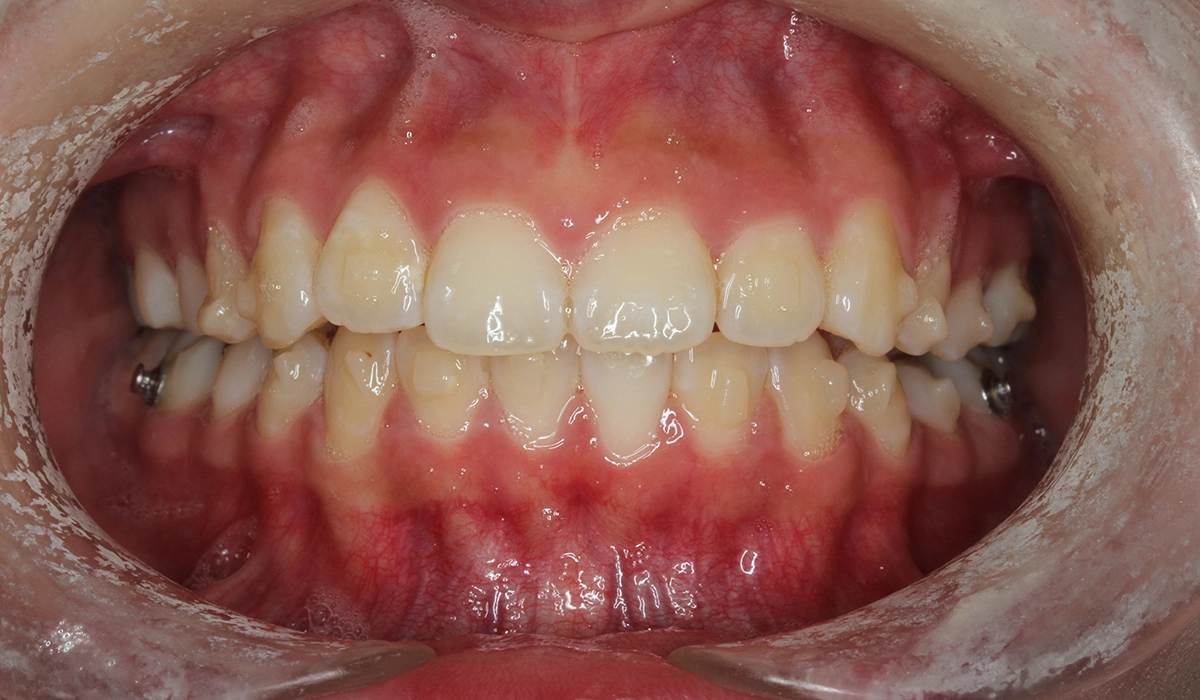

術前:正面

術後:正面